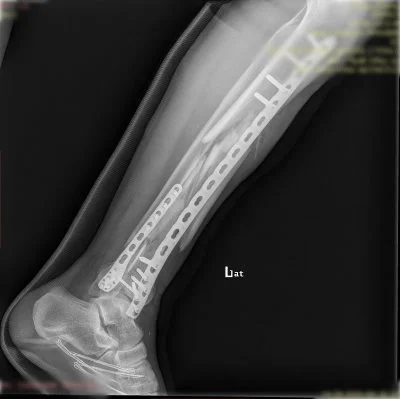

Görüntüleri büyütmek için resmin üstüne tıklayınız.